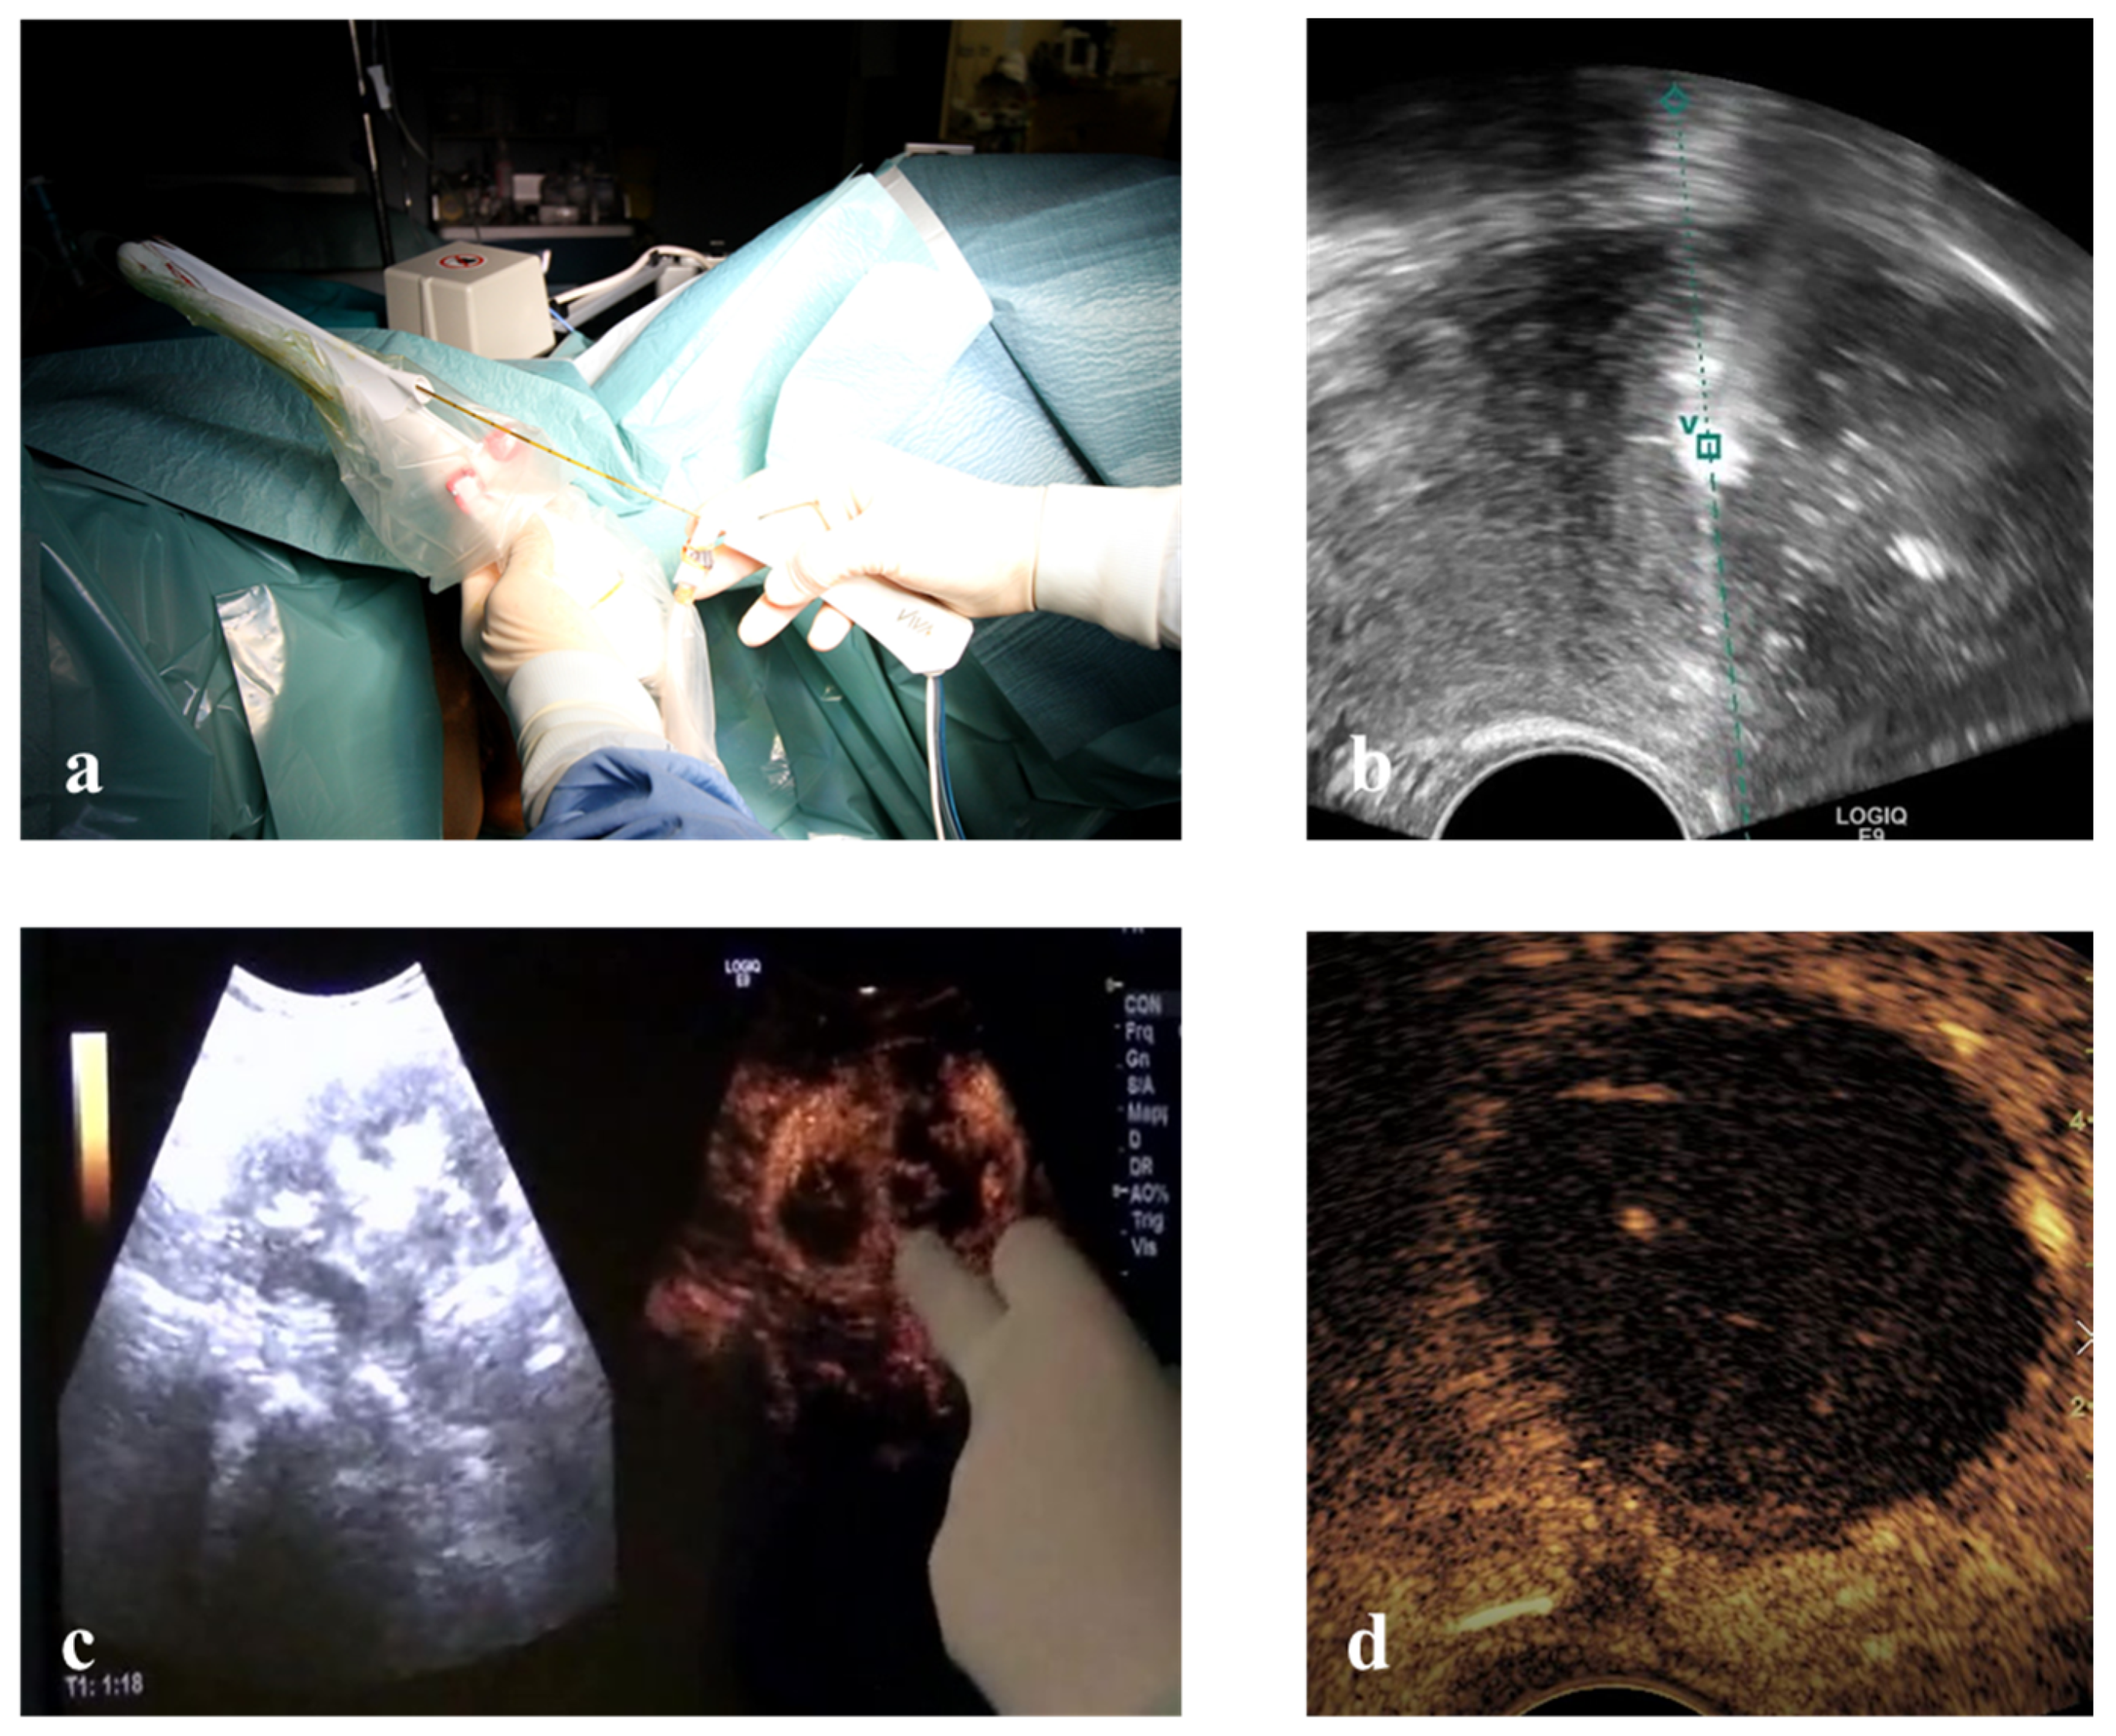

Hysteroscopic RFM: unconscious sedation or spinal anesthesia and dorsal position were performed on an outpatient basis. Standard hysteroscopic instrumentation (Outer diameter 3.8 mm and straight 5 French (Fr) working channel, Wolf Medical Instruments, Germany) (Figure 4), and trans-abdominal ultrasonography for intra-uterine needle guidance.

Figure 4. (a) RF electrode inserted into 5 Fr. working channel of a 3.8 mm hysteroscope. (b) and (c) Intra-operative TA ultrasound shows hyper-echogenicity of RF ablation of an anterior myoma (arrowheads) between the bladder (asterisk) and the endometrial cavity (empty point). (d) Echo-enhanced area after complete RF ablation of the fibroid.